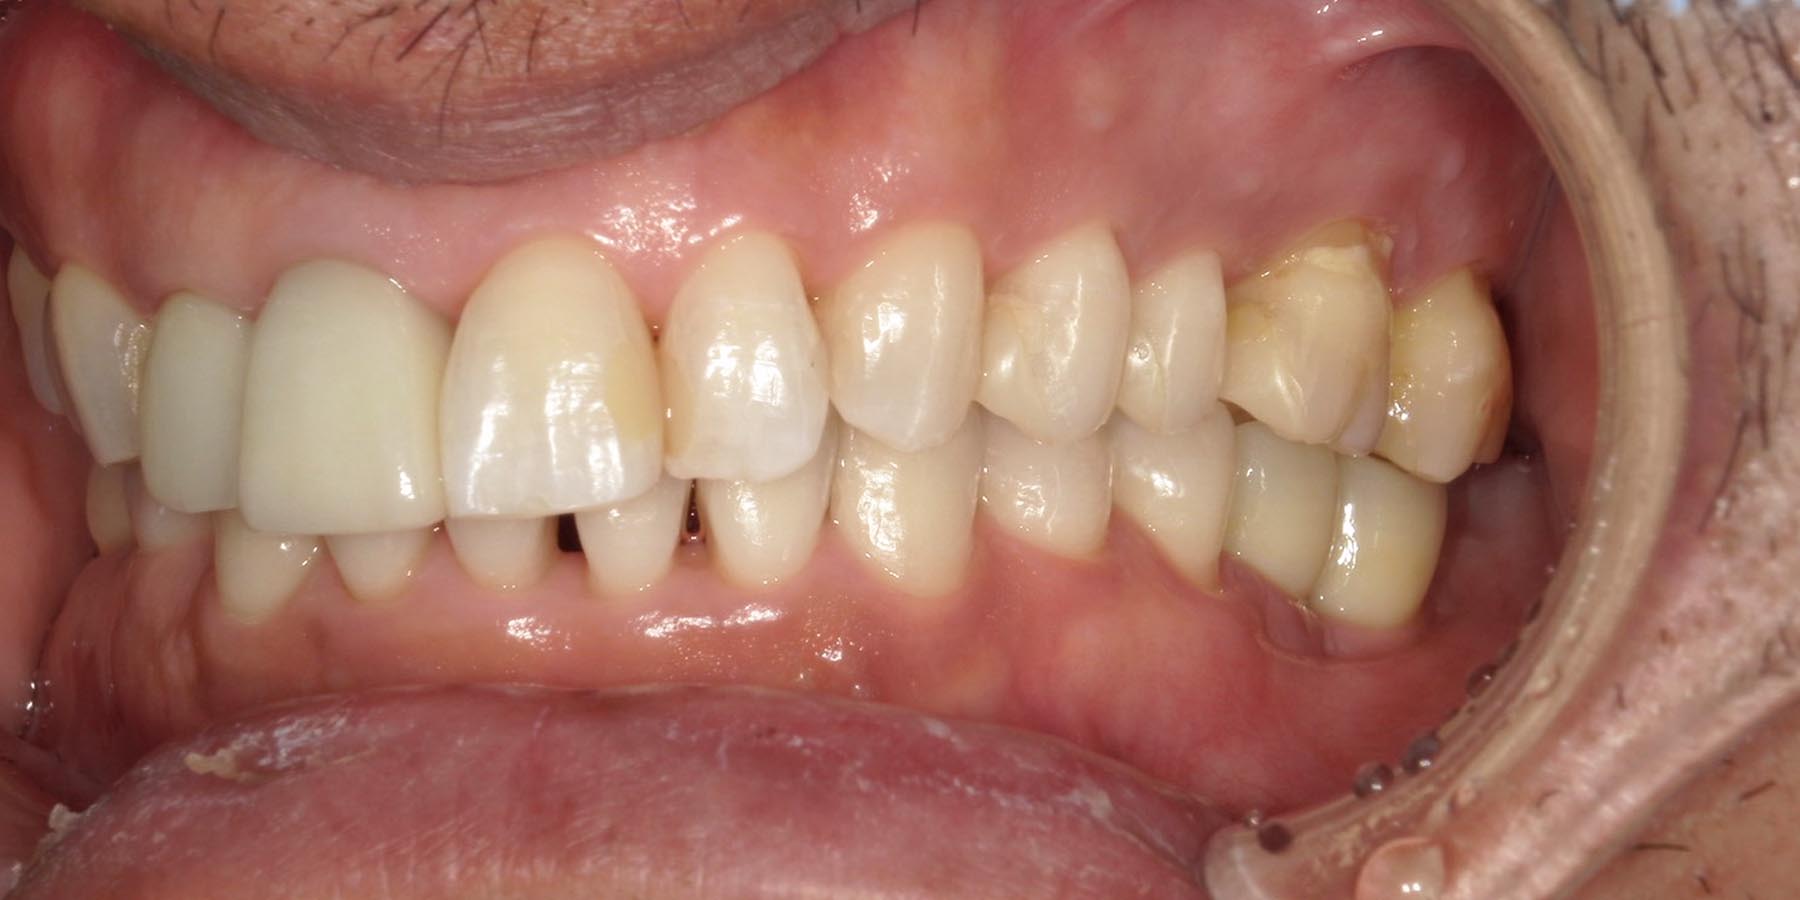

治療後